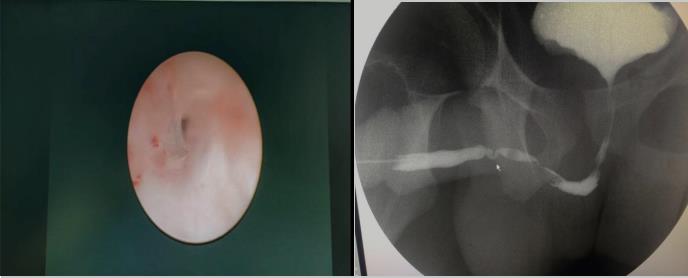

內蒙古17歲的高三學生小馬,10年前做闌尾切除手術,術后因留置尿管,逐步出現排尿不暢,從站立時排尿滴瀝,尿線細,到站立時無法自解小便,后逐漸養成蹲位排尿習慣。正值高三關鍵階段的小馬,自覺排尿不暢較前明顯加重,已嚴重干擾平日學習和生活,痛苦不堪。父母帶小馬先后在內蒙、上海等地就診,后經親戚介紹,在我院泌尿外科入住。入院后強永春主任了解其病情后,通過尿流率檢測、尿道鏡檢查及尿道造影,明確患者前尿道兩段狹窄。與家屬充分溝通后,泌尿外科團隊精心術前準備,在全麻下行“頰粘膜尿道成形術”,術中證實前尿道兩處狹窄,狹窄段長8㎝,取兩側頰粘膜各4×1cm,重建修復尿道狹窄。術后第2天,患者可進少量流食,說話正常,術后1周患者帶管好轉出院,出院3周患者來院復查,主管醫師張順給予拔除尿管后,小馬終于露出久違的笑容:“終于可以站著排尿了”。術后站立位查自然尿流率示:最大尿流率 19.2ml/s。手術效果滿意。

強永春副主任介紹說:尿道狹窄最常見的癥狀是尿流減少和膀胱不完全排空,也可以表現排尿困難、尿路感染、附睪炎、殘余尿量多。該患者考慮為尿路感染所致。尿道狹窄以往采用尿道擴張、內鏡切開及尿道成形術治療,但長段的狹窄手術后效果并不滿意,現在有了粘膜組織移植,組織移植常選擇口腔粘膜(頰粘膜、舌粘膜和唇粘膜),手術效果好,但手術要求高,難度大。